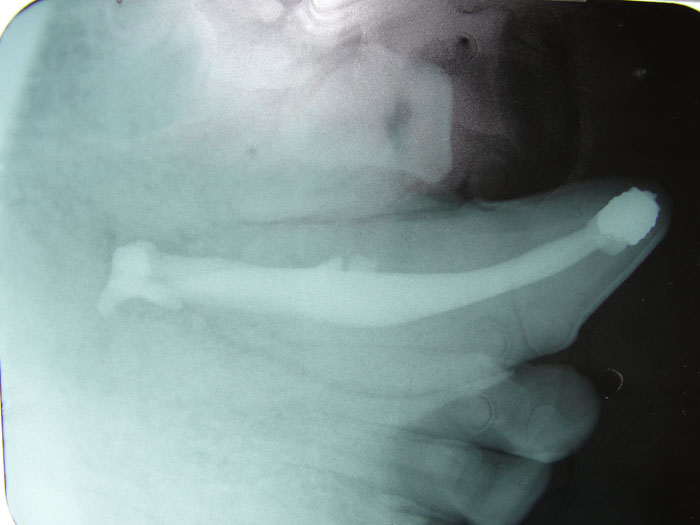

The Large Volume Veterinary Endodontic Syringe™ is an endodontic syringe developed by Dr. John Scheels specifically for veterinary use in all species for complete and consistent obturation of root canals over 30mm long or with large pulp chambers.

It permits the positive deposition of endodontic sealer and filler pastes at the apex of these long teeth. NO SPECIAL NEEDLES are required as it may be used with any standard size hub. Plastic, metal, threaded or non-threaded needle hubs will seal well on the tapered syringe nipple.

Mix enough paste to more than fill the canal and chamber. A 2" or 3" 18 gauge needle is a good choice for reaching the apex of the root canal in cases such as large canid or felid cases.

Fill the needle hub with paste. Attach the hub to the syringe and thread on the needle. Either plastic or metal, threaded or non-threaded needle hubs will seal well on the tapered syringe hub nipple. Place the plunger into the syringe and engage the threads. Turn the plunger to extrude the paste from the needle.

After drying the prepared canal, fit the master gutta percha cone in the canal. Place the needle into the canal all the way to the apex. Turn the plunger slowly and withdraw the needle as the root canal and chamber are filled with paste. Gutta percha points may also be used to aid in condensation and complete obturation as desired. A firm base should be placed over the fill, such as zinc phosphate cement. Then a final restoration material of choice is placed.